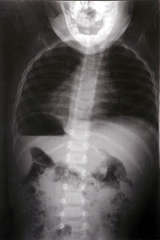

�J平成22年2月17日レントゲン検診

装具外して7度・4才5ヶ月

平成22年7月29日来院

正常範囲と診断 4歳9ヶ月

�J平成22年2月17日レントゲン検診 装具を外して7度。4歳5ヶ月。